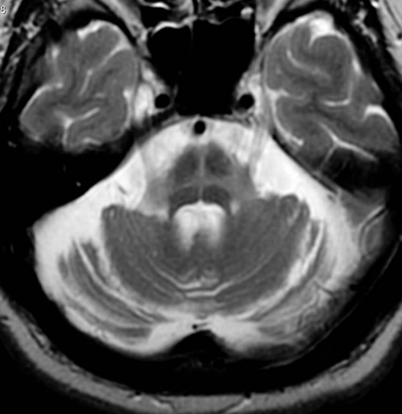

hot cross bun sign

hyperintensities of cerebellar peduncles